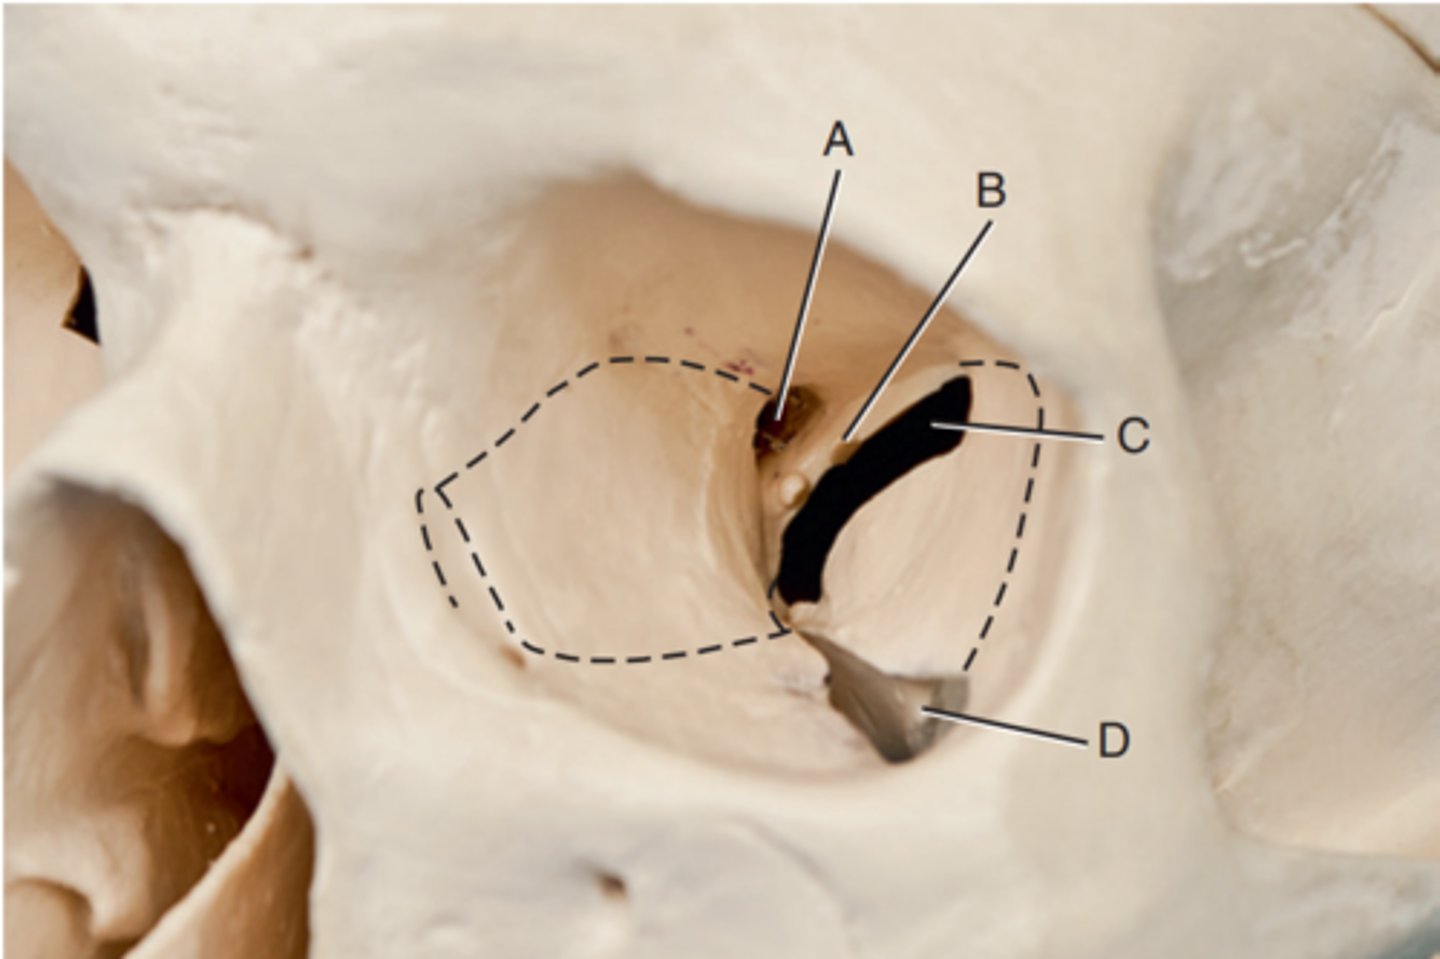

Optic foramen

Label A

Sphenoid strut

Label B

Superior orbital fissure

Label C

Inferior orbital fissure

Label D

Orbital plate of frontal bone

Label A

Sphenoid bone

Label B

Optic foramen and canal

Label C

Superior orbital fissure

Label D

Infraorbital margin (IOM)

Label E

Sphenoid strut

Label F

Lateral orbital margin

Label G

Supraorbital margin

Label H